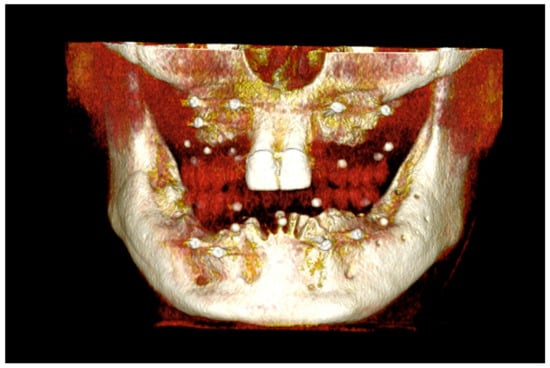

The number, the length, the diameter and the placement of computational virtual implants were determined with respect to the design of the final prosthesis the available residual bone volume and the anatomical limitations according to the previously described technical procedure (Figure 16, Figure 17, Figure 18, Figure 19, Figure 20 and Figure 21).

Figure 16.

Three-dimensional (3D) CBCT scan images with the patient wearing the planned prosthesis.

Figure 17.

Three-dimensional (3D) CBCT scan images of the prosthesis equipped with integrated radiopaque reference spheres scanned separately.

Figure 18.

Three-dimensional (3D) planning of the number, the diameter and the axis of dental implants with respect to the design of the final virtual maxillary prosthesis.

Figure 19.